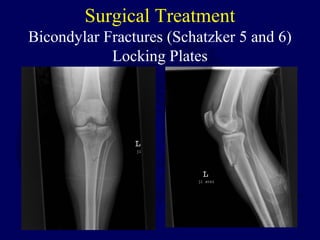

Bicondylar Fractures (Schatzker 5 and 6)

Locking Plates

Surgical Treatment